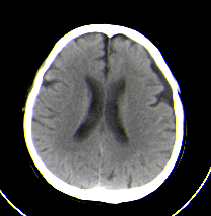

本例左侧额颞部内板下新月形低密度影分布,邻近脑组织轻度受压;脑萎缩应该有脑沟相对宽深的表现,而本例病人额叶的脑沟是受压闭塞的。所以考虑为硬膜下积液。

左侧额颞部颅骨内板下新月形液性密度影,

意见:左侧额颞部硬膜下积液.